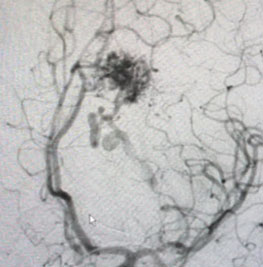

Angiogram (Figure 3 and 4) confirmed the presence of a deep left frontal AVM without any associated aneurysms.

Fig. 4